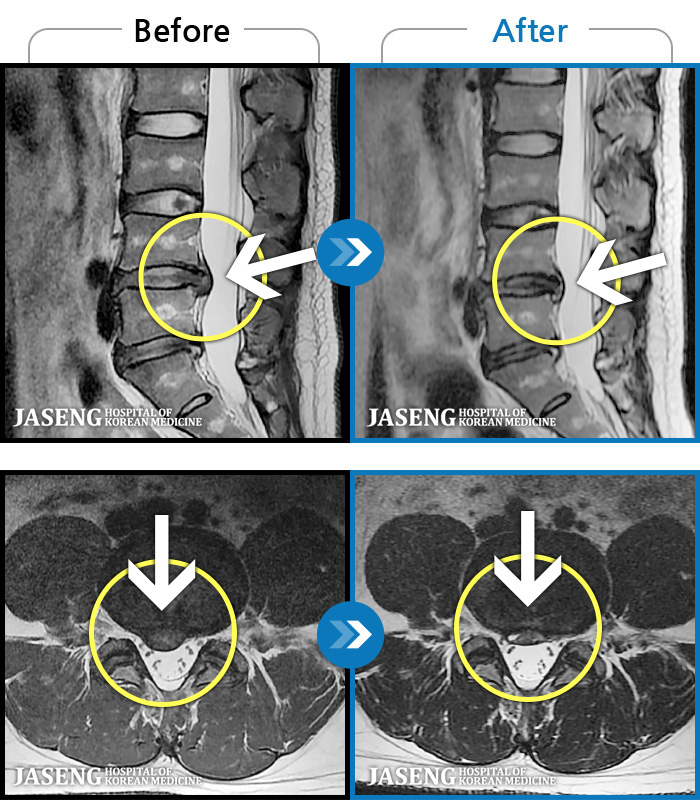

[] 03.04.01~09.11.01